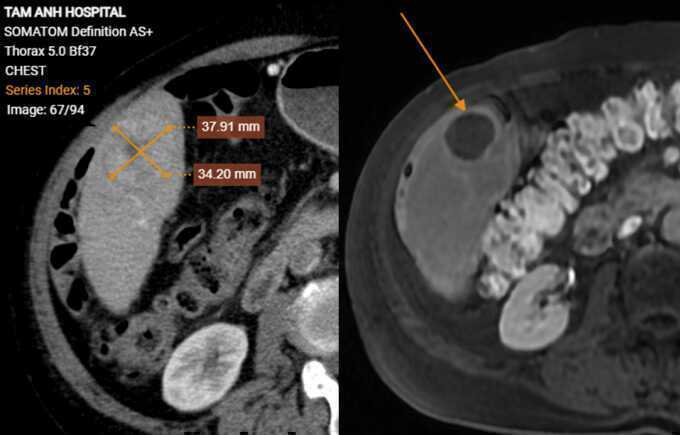

Ông Phong không có triệu chứng bất thường, siêu âm tầm soát ung thư gan do hút thuốc hơn 30 năm, tiền sử xơ gan, viêm gan siêu vi B, kết quả có khối giảm âm trong gan. Xét nghiệm máu ghi nhận mức AFP (chỉ điểm ung thư gan) trên 1440 ng/ml, gấp hơn 200 lần ngưỡng bình thường. Ảnh chụp CT phát hiện hai khối u gan kích thước 15x20 mm và 37x34 mm, bệnh nhân còn bị lóc tách động mạch chủ ngực, xơ vữa, phình, giãn một số động mạch chủ khác và hẹp 56% gốc động mạch thân tạng.